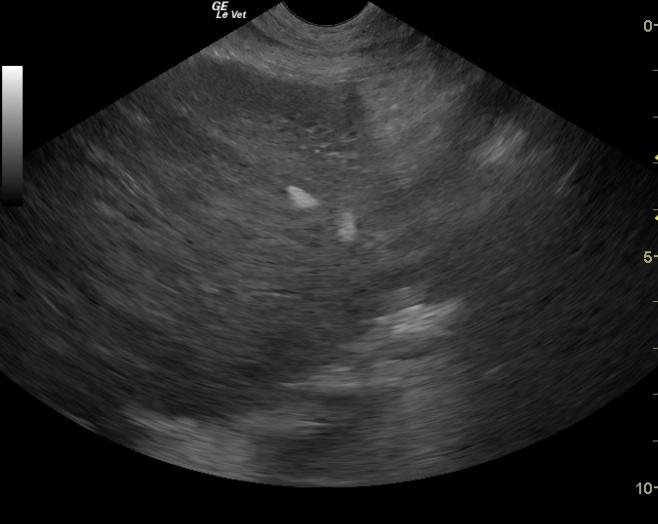

The liver presented swollen but regular contour and micronodular changes with reactive pericapsular omentum. Echogenic free fluid was present suggestive for hemorrhage or peritonitis. Adhesions along the small intestinal border are represented by hyperechoic fat attached to the intestinal serosa and move with the intestine.

Lobar liver swelling consistent with hepatoma or low grade neoplasia. Post operative peritonitis with potential perforation and adhesions.